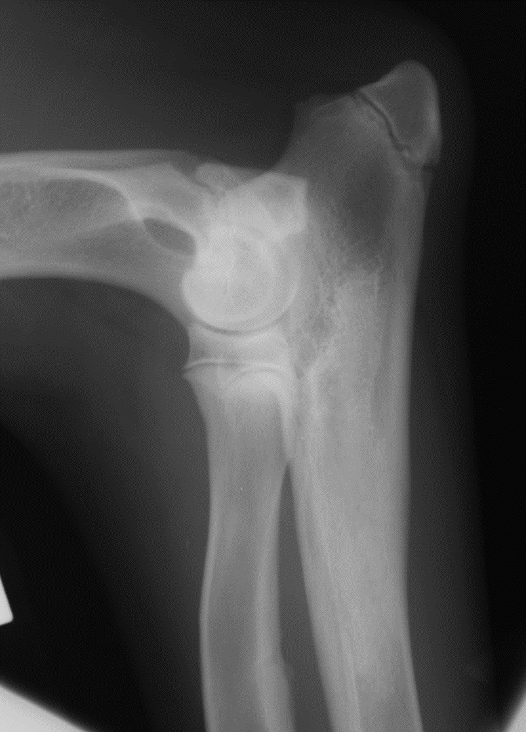

which OCD lesions are these in the dog

A = cd humerus

B = medial humeral condyle (elbow)

C = medial trochlear ridge (ankle)

D =lateral femoral condyle (knee)